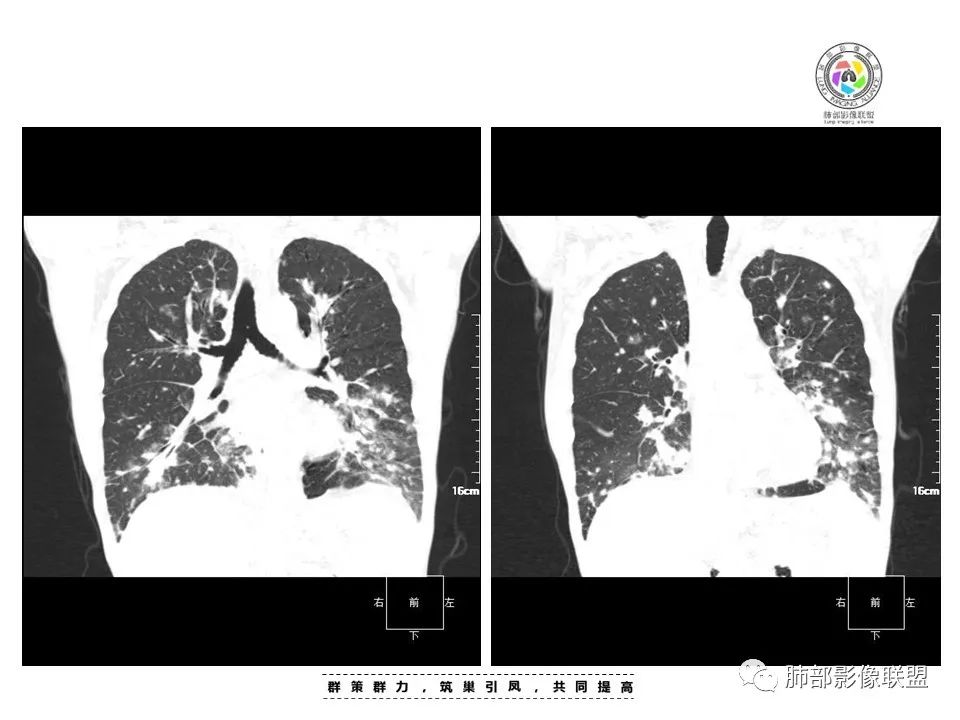

两肺弥漫性性结节状、小片状及片状带晕的病灶,煎蛋征、点晕征,主要分布两肺中下叶,病灶周围小叶间隔增厚呈网格状影,部分病灶累及胸膜,伴两侧胸膜增厚。

2.本例双肺小叶间隔增厚明显,多发结节影及片状实性密度影,沿血管支气管束分布为主,两侧较为对称,病灶多环以磨玻璃晕,边界不清。

双侧胸腔少量积液。双肺门及纵隔未见明确肿大淋巴结,纵隔结构间隙模糊。

3.有学者将这种具有沿双肺支气管束分布的实性密度片影描述为“火焰征”,认为具有一定特征性,单就影像表现而言,这种影像表现也可以见于其他病损或多种病理改变的叠加。

1.结节型:两肺沿支气管血管束分布的结节影,呈火焰状或星芒状、挂果征,局部周围出血磨玻璃影(肺泡出血或水肿)。

2.支气管血管束增粗型:

肺门周围支气管壁呈“套袖样”改变。

3.肺炎渗出型:

斑片渗出影,部分融合呈“火焰样”,同时有火焰样结节,小叶间隔增厚等表现。

还可以有纵隔及腋下淋巴结增大,胸腔积液等表现。